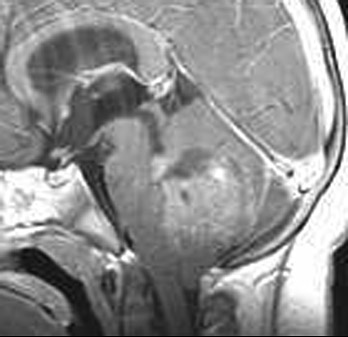

This sagittal T1 weighted MRI scan demonstrates a

medulloblastoma

of the cerebellar vermis that is producing obstruction to CSF flow in the fourth ventricle, leading to

hydrocephalus

.